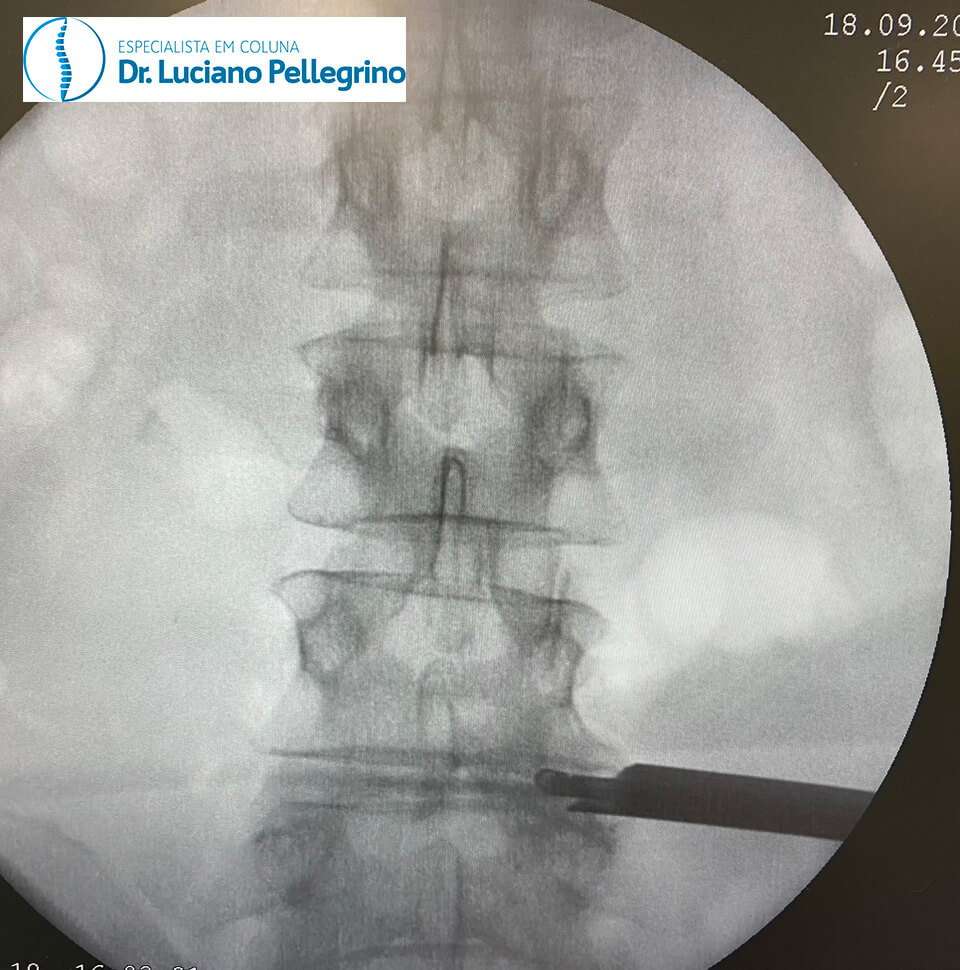

O uso da técnica da endoscopia de coluna se dá através do uso de uma pequena câmera e pequenos instrumentos cirúrgicos (para inserirmos a cânula no local correto antes de entrar com o endoscópio, fazemos uso da radioscopia, como indicado nas figuras abaixo).

Em grande parte dos casos, é realizada uma incisão mínima (cerca de 8 milímetros) na coluna do paciente, com o mesmo sob anestesia geral ou sedação.

A magnificação obtida pela ótica da microcâmera permite a visualização das estruturas anatômicas com alta precisão e com muito menos sangramento do que a cirurgia convencional, pois há a infusão contínua de soro fisiológico pela cânula.